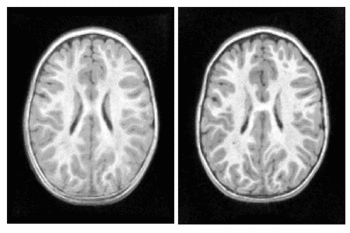

Pediatric Brain Development

We explore the impact of joint image and shape regression in modeling pediatric brain development. The data consists of T1W images of the same healthy child observed at 6, 12, and 25 months of age. Regression on images alone is difficult in this case due to the very low contrast in the 6 month old image. Despite the low contrast, tissue segmentations can still be reliably and consistently estimated [10]. We estimate a geodesic model using only T1W images and a model jointly on images and white matter surfaces to emphasize the development of the tissue interface.

The results of geodesic regression are shown for several snapshots in time in Fig. 4. The model estimated using only images mostly captures the scale change, but does not capture much deformation in the interior of the brain. The model estimated jointly on image and shape captures more detailed development as white matter stretches and expands.